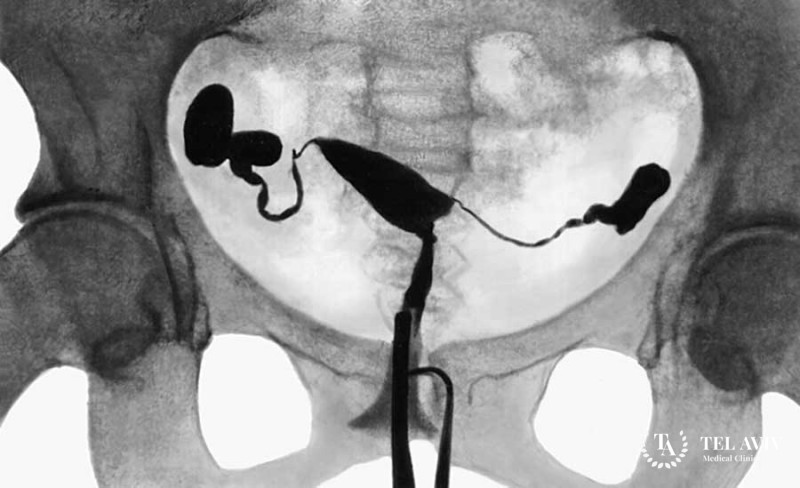

Популярность ГСГ состоит не только в ее способности визуализировать обследуемые органы, но и в выполнении лечебной функции. Во время манипуляции маточные трубы заполняются специальным, подогретым веществом, движение которого по трубам и должно показать их проходимость. Иногда, если помехи в полости маточных труб были незначительные, применение ГСГ производит терапевтический эффект. Спайки под давлением жидкости разрываются, улучшая проходимость канала, и уже не мешают женщине зачать ребенка.

Техника является безболезненной, не требует использования анестезии и госпитализации. Длится она около 30 минут. Пациентке, которая находится в горизонтальном положении, в канал шейки матки вводится гибкий катер. По нему в трубы поступает жидкость, выпущенная под достаточным напором, чтобы убрать спаечные образования и вернуть женщине репродуктивную функцию.